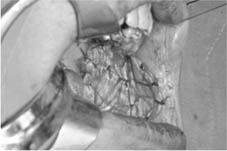

病例一

右頰側惡性腫瘤

腫瘤切除後之傷口

以冷凍乾燥異體肌膜修補傷口

傷口施以壓迫一週

六週後傷口癒合良好

仍然維持正常開口度